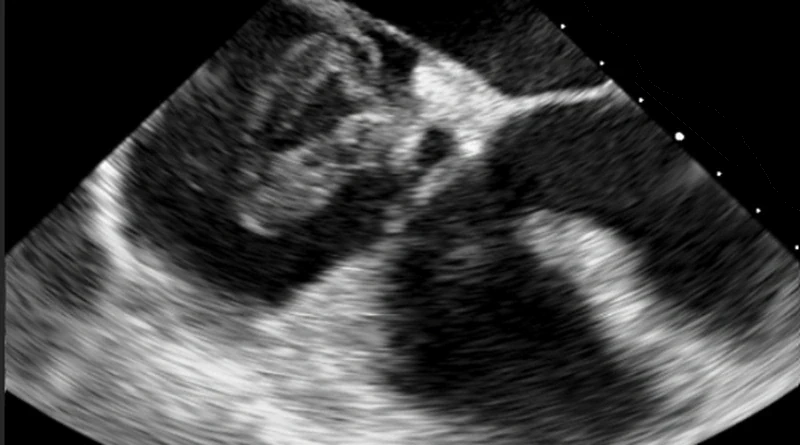

Echocardiogram

There are less common ways to diagnose clots. One is with an echocardiogram. While this study looks at the heart chambers and valves, it can also show clots in the heart. An echocardiogram is practically the most accurate way to diagnose a clot in transit. This is a clot on its way from the legs to the lungs, through the heart.

If we identify a clot in transit with echocardiogram, it is important to also look for a patent foramen ovale. A patent foramen ovale, or PFO, is a hole between the heart chambers. A clot in the heart may pass through a PFO. If that happens, it might skip the lungs and cause a stroke, which in the end is an artery blood clot.